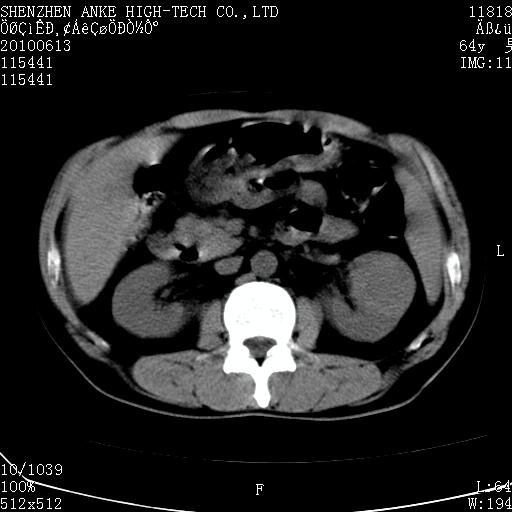

以下是引用beifangren在2010-7-26 22:05:00的发言:[br]左肾中极圆形占位,肾盏肾盂受压移位,建议增强。结合肺部结节。肝低密度灶,多为肾癌并肺部、肝转移。